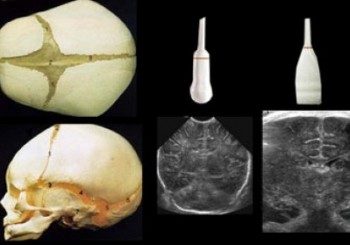

Transfontanel Ultrason

ayrıntılı ultrason

Transfontanel Ultrason Nedir? Yenidoğan döneminde bebeğin beyin yapılarının radyasyon olmadan değerlendirilebilmesini sağlar. Kullanım alanları, hastanın şikâyetleri ve klinik bulgular birlikte değerlendirilerek klinisyen ve uzman radyolog işbirliği ile genişletilebilir. Transfontanel ultrason ile beyin içi incelemesi yapılır. Böyle bir durumda akla neden MR ya da bilgisayarlı tomografi kullanılmadığı gelebilir. Öncelikle hastanın bebek olması ve hareketsiz duramaması nedeniyle MR veya Tomografi...

Devamı